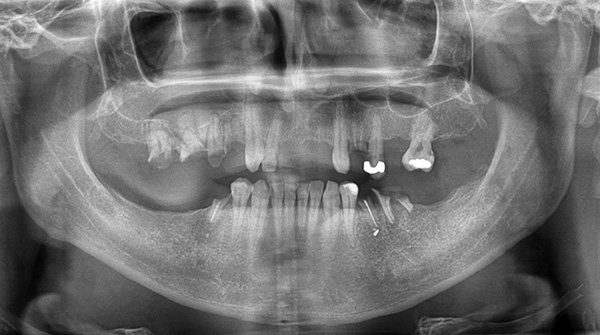

В настоящее время это осложнение имплантации встречается намного реже, чем бывало раньше. Прогресс произошел во многом благодаря возможности точно определить расстояние до полостных образований с помощью панорамных снимков и компьютерной томографии (КТ).

Для построения плана операции пациент проходит рентгеноскопию, показывающую толщину и целостность кости челюсти. В результате выявляются противопоказания к имплантации и скрытые проблемы, в число которых входит и кариес.